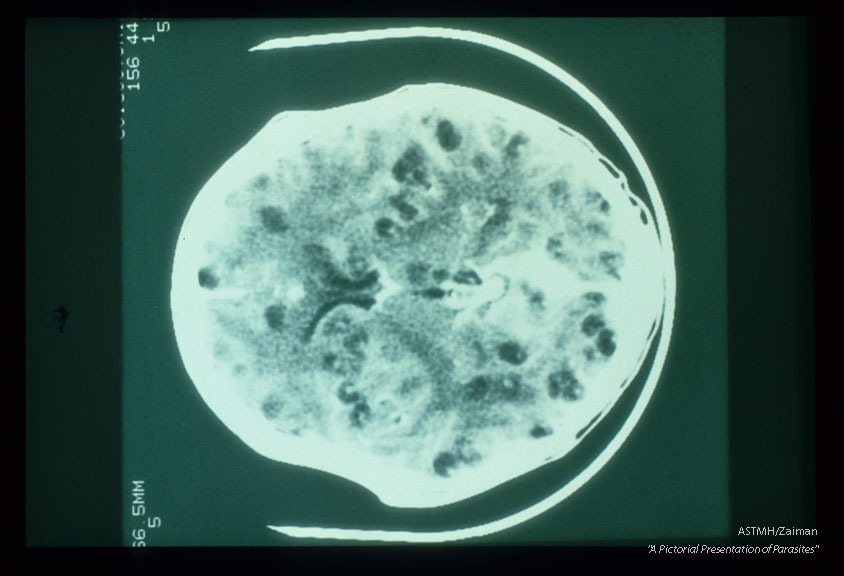

A CAT scan of the skull shows multiple small, rounded, dark lucencies in the brain. These are cysticerci. Some show central, white calcific dots which are scolices. Some show peripheral calcifications. Midline bird-like and linear dark lucencies represent the ventricular system. Midline white calcific densities are probably vascular structures.

Taenia solium